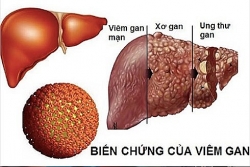

Ung thư gan là gì? Nguyên nhân, triệu chứng và cách điều trị ung thư gan

Ung thư gan là bệnh ung thư phổ biến thứ 5 ở nam giới và là bệnh ung thư phổ biến thứ 9 ở phụ nữ. Theo World Cancer Research Fund, Việt Nam là nước đứng ...